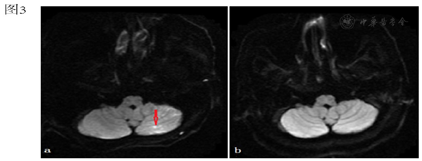

患者女性,76岁,2020年4月外院检查时发现右肺占位,胸部CT提示:右肺上叶前段,混杂磨玻璃密度,边缘毛糙,见多发毛刺,邻近胸膜受轻度牵拉,病灶范围约2.7×1.6 cm(图1),否认发热、胸闷、憋气、咯血等症状。患者2021年6月为行肺穿刺活检就诊我院。既往有高血压病史5年,口服药物治疗,血压控制尚可。个人史、家族史、月经婚育史无殊。完善术前检查除外禁忌后,于2021年6月22日在局部浸润麻醉下行CT引导下右肺穿刺活检术,过程顺利,术后复查CT,无气胸征象,可见局部少量出血。患者起身时出现咳嗽伴咯血,约3~5 ml,随即出现头晕,意识不清,给予吸氧、补液等对症处理后返回病房,回病房后患者意识转清,但反应迟钝,言语不清,伴间断四肢抽搐。体格检查:双侧瞳孔等大等圆,对光反应灵敏,伸舌居中,左上肢近端及远端肌力0级,右上肢近端及远端肌力4级,双下肢肌力4级,四肢肌张力正常,双侧病理征可疑阳性。2小时后患者再次出现意识不清,仍有间断四肢抽搐。

行心电图:窦性心律,T波改变;急查血常规、凝血功能、降钙素原、心肌损伤标记物、BNP未见明显异常。血气分析:酸碱度7.345,二氧化碳分压45.7 mmHg,氧分压74.4 mmHg,乳酸2.1 mmol/L;胸部CT提示:左心室腔可疑气体影(图2)。颅脑CT未见异常,急诊颅脑MRI示:左侧额颞顶枕叶、右侧额顶叶及其皮层下、左侧小脑半球多处新发脑梗死灶(图3a、图4a、图5a)。颈动脉超声:双侧颈动脉内膜增厚。患者同日转入ICU进一步治疗,入室体格检查:T 37.8℃,P 87次/分,R 15次/分,BP 190/109 mmHg,鼻导管吸氧,血氧饱和度98%。浅昏迷状态,GCS评分:E2V2M4,双侧瞳孔等大等圆,直径约2 mm,光反射迟钝。双肺听诊呼吸音清,心脏听诊律齐,未闻及杂音及额外心音。四肢肌张力增高,双侧巴氏征阳性。